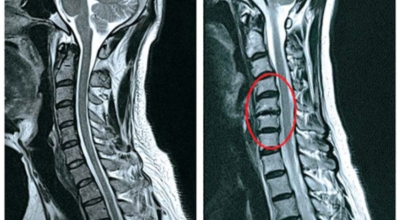

경추 사이의 추간판(디스크)이 탈출 또는 파열되어 경추신경이 자극이나 압박을 받아 통증이 생기는 증상을 말해요. 경추는 운동성이 큰 부위로 추간판이 압력을 받으면 튀어나와 척수나 신경을 압박하게 되는데요 목디스크는 퇴행성 변화 이후에 발생되기 때문에 많은 환자들이 만성적인 통증을 지니고 있는 경우가 많습니다.

디스크의 수핵이 빠져나가거나 퇴행성 경추 척추증 또는 경추관협착증 등으로 척수가 눌리게되면 대부분이적으로는 팔의 힘이 빠지는 느낌을 받을 수 있답니다. 척수가 눌린 정도에 따라서는 한쪽 팔만 마비되기도 해요. 하지만 양쪽 팔의 감각이 둔해지고 눈을 감으면 무질서하게 되는 경우도 있어서 이러한 목디스크 증상이 나타나면 매우 위험한 상태이니 빠른 치료가 필요해요.